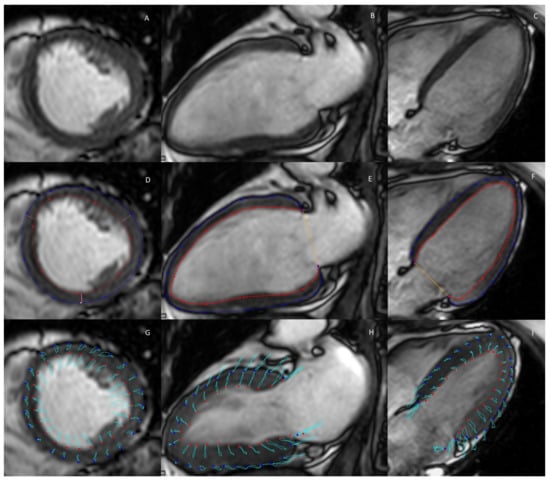

2.1. Cine MRI

2.5. D Flow Measurements